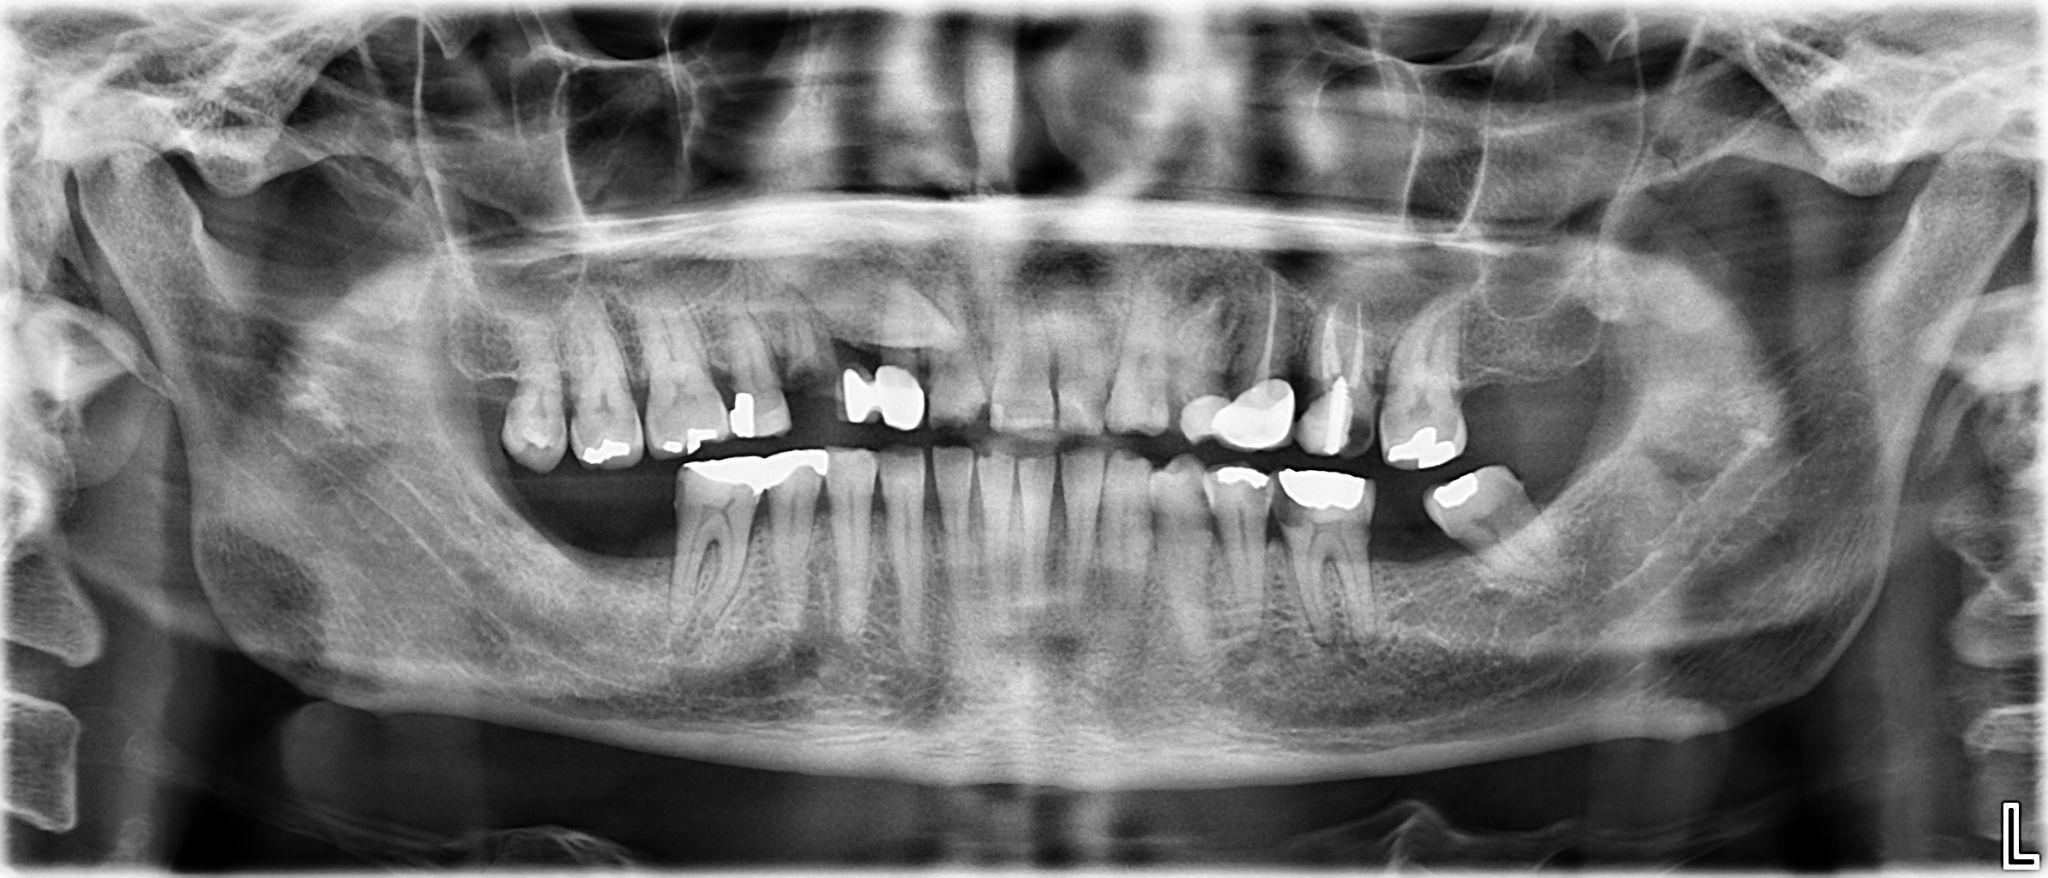

1. What options can be selected for the first quadrant of this panoramic X ray?

2. What options can be selected for the second quadrant of this panoramic X ray?

3. What options can be selected for the third quadrant of this panoramic X ray?

4. What options can be selected for the forth quadrant of this panoramic X ray?